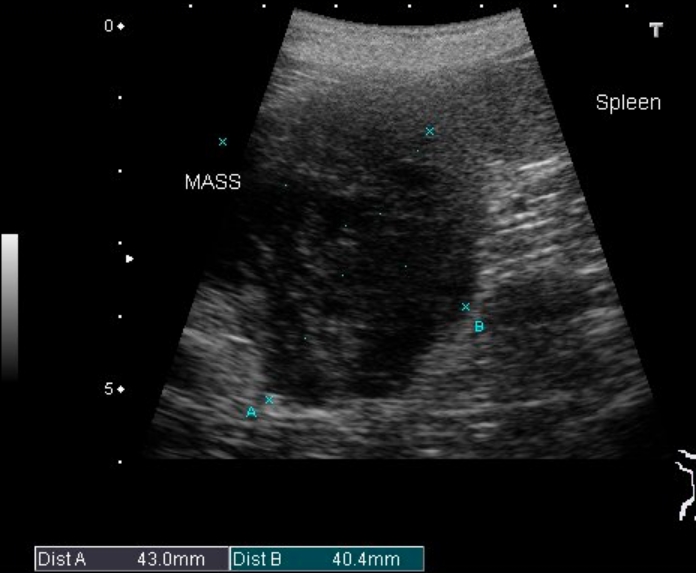

脾臓腫瘤

脾臓は体の左側で胃の後方にあります。

働きとしては ①赤血球の貯蔵 ②赤血球の破壊 ③免疫があります。

血液が非常に多いのでそれに関連した病気も多く認められます。 その代表的な病態として腫瘤形成があり、この腫瘤の正体は血腫と言われる血液の塊から血管肉腫と言われる悪性腫瘍まで様々です。しかし、この腫瘤が徐々に拡大し破裂を起こすと正体に関わらずお腹の中で大量の出血を起こすので、貧血・食欲不振・虚脱場合によっては亡くなることもあります。しかしながら破裂する前はいつも通り元気なことが多いのでの発見が遅れてしまい、破裂し虚脱状態で病院に来るのが現状です。

実際の症例

9歳のM.ダックス、チョロちゃん。

下痢を主訴に来院されました。経緯や状態を診て一過性の下痢と思われたので治療を開始しました。

実はこの時身体検査でお腹の中に腫瘤病変を触知したので、下痢が良化したら腫瘤病変の検査を行うことにしました。数日で下痢はよくなったので腫瘤の検査を行いました。

各種検査の結果、脾臓に4cm大の腫瘤が形成されていました。

元気も食欲もあり貧血などの状態もありませんでした。

飼い主様には偶発的な発見であり状態はかなり良いことや破裂の危険性に関してお話をさせていただき手術の同意を得ることができました。

• エコー画像